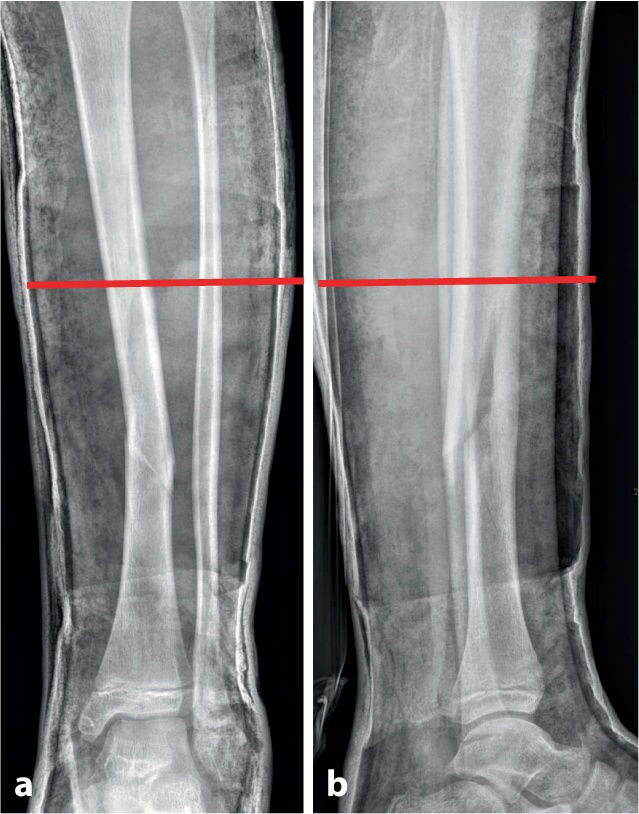

Abb. 3

Durchführung der Gipskeilung am Unterschenkel. Knabe, 11 Jahre, Sturz beim Skifahren. Tibiaspiralfraktur Übergang mittleres in distales Schaftdrittel mit Grünholzkomponente an der Fibula. Am 8. Tag nach Trauma erfolgt eine radiologische Stellungskontrolle, bei der sich eine Dislokation in den Varus und eine Retrokurvationsstellung zeigen. Zunächst Analyse der Keilungsrichtung, die Wirkung des Keils muss in der maximalen Konkavität der Frakturfehlstellung(en) zum Tragen kommen. Zur Korrektur eines isolierten Varus erfolgt die Keilung von medial (a), die Beseitigung einer alleinigen Retrokurvation gelingt durch Keilung von ventral (b). Deshalb wird im angeführten Fall die Stellungskorrektur durch Aufdehnen des Gipsverbandes von ventromedial geplant (c)

Abb. 4

Als nächster Schritt wird die Höhe des Keils bestimmt, die bei diaphysären Quer- und kurzen Schrägfrakturen direkt über dem Bruch und bei längeren Spiralfrakturen am proximalen Bruchende liegt. Im distal metaphysären Bereich Positionierung des Keils rund eine Handbreite proximal der Fraktur. Da die genaue Lokalisation mitentscheidend für das Gelingen des Keilens ist, sollte, zumindest bei anspruchsvollen Keilungen (oder beim Ungeübten), die Bestimmung der Keilungshöhe unter Bildwandlerkontrolle erfolgen. ab Keilungshöhe am proximalen Frakturende